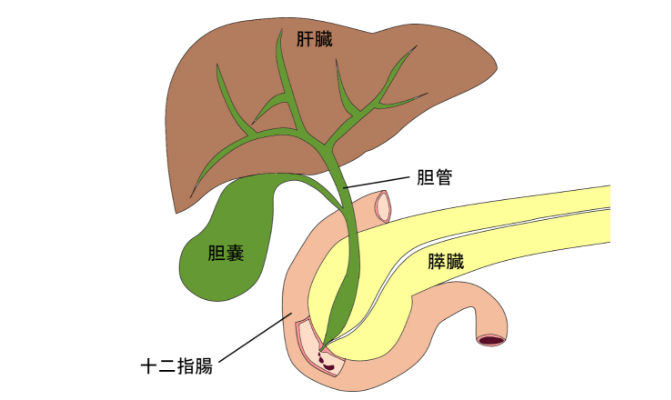

胆嚢は、肝臓の下、腹部の上部、右側に位置する臓器です。基本的に、腸が脂肪を消化して吸収する必要があるときに、肝臓で生成された胆汁を放出するための貯蔵場所として機能します。